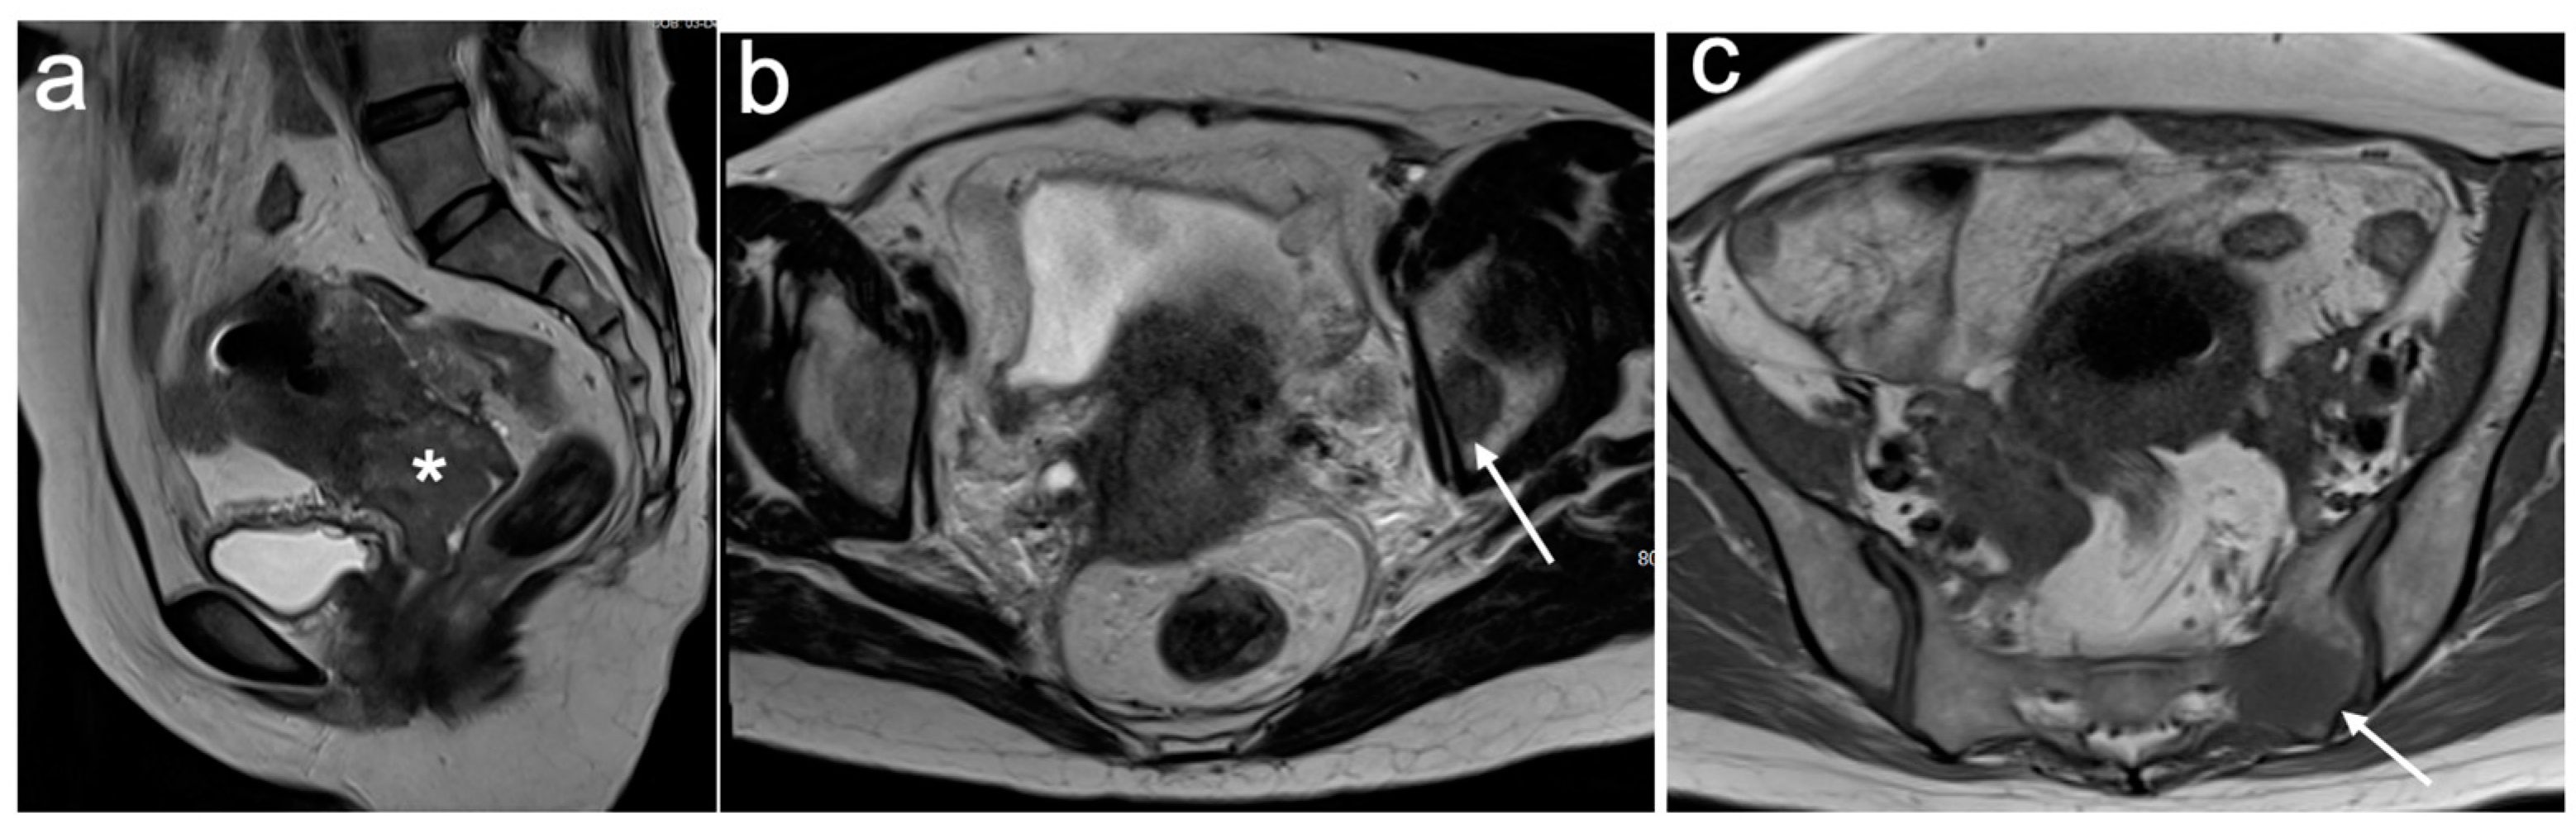

4. FIGO Stage I

| Stage I | The carcinoma is strictly confined to the cervix |

| IA | Invasive carcinoma that can be diagnosed only by microscopy with a maximum depth of invasion <5 mm |

| IA1 | Measured stromal invasion <3 mm in depth |

| IA2 | Measured stromal invasion 3 mm and <5 mm in depth |

| IB | Invasive carcinoma confined to the uterine cervix with measured deepest invasion 5 mm |

| IB1 | Tumour measures <2 cm in greatest dimension |

| IB2 | Tumour measures 2 cm and <4 cm in greatest dimension |

| IB3 | Tumour measures 4 cm in greatest dimension |

- McEvoy, S.H.; Nougaret, S.; Abu-Rustum, N.R.; Vargas, H.A.; Sadowski, E.A.; Menias, C.O.; Shitano, F.; Fujii, S.; Sosa, R.E.; Escalon, J.G.; et al. Fertility-sparing for young patients with gynecologic cancer: How MRI can guide patient selection prior to conservative management. Abdom. Radiol. 2017, 42, 2488–2512, Erratum in Abdom. Radiol. 2017, 42, 2966–2973. [Google Scholar]

- Halaska, M.; Robova, H.; Pluta, M.; Rob, L. The role of trachelectomy in cervical cancer. Ecancermedicalscience 2015, 9, 506. [Google Scholar] [CrossRef]

- Rockall, A.G.; Qureshi, M.; Papadopoulou, I.; Saso, S.; Butterfield, N.; Thomassin-Naggara, I.; Farthing, A.; Smith, J.R.; Bharwani, N. Role of Imaging in Fertility-sparing Treatment of Gynecologic Malignancies. Radiographics 2016, 36, 2214–2233. [Google Scholar] [CrossRef] [PubMed]

- Noël, P.; Dubé, M.; Plante, M.; St-Laurent, G. Early cervical carcinoma and fertility-sparing treatment options: MR imaging as a tool in patient selection and a follow-up modality. Radiographics 2014, 34, 1099–1119. [Google Scholar] [CrossRef] [PubMed]